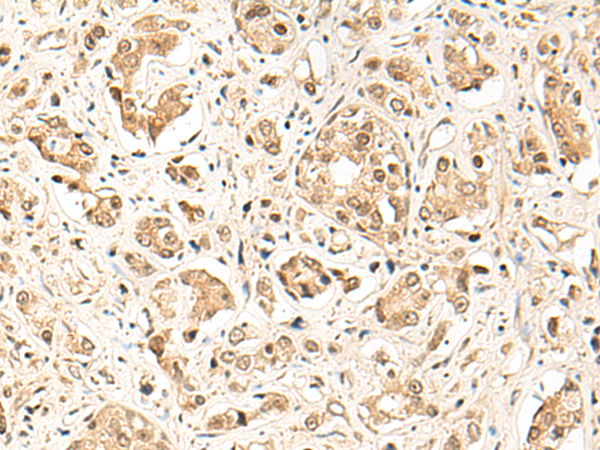

IHC positive control:

Human lung cancer and Human prostate cancer